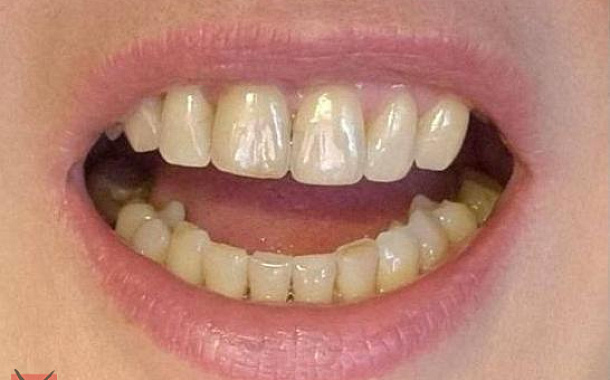

Возвращение эстетики улыбк.

Если имплантация проводится в районе передних зубов -

Одномоментное удаление и установка зубного импланта в лунку помогают сократить до минимума костно-пластические и мягкотканные манипуляции, сохранить анатомию гребня альвеолярного отростка и сформировать естественный профиль прорезывания искусственной коронки, то есть создать иллюзию своего зуба.